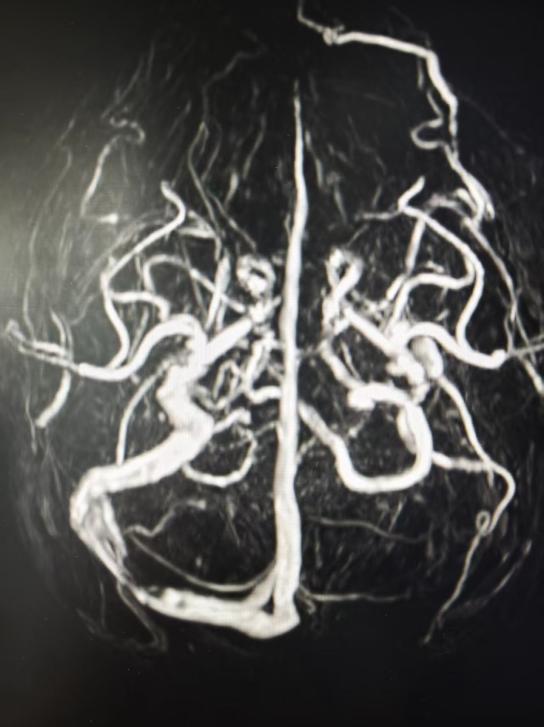

患者系26岁男性,发作性头痛1周余。术前感染、免疫、生化及脑脊液常规检查无明显异常。行头部MRV检查,显示左侧横-乙状窦发育纤细、右侧横窦局限性狭窄,考虑为特发性颅高压伴静脉窦狭窄。

神经内二科团队分析讨论后,为患者实施了静脉窦造影术+测压+血管内超声检查。造影提示右侧横-乙状窦交界区局限性狭窄,测压提示狭窄近-远端压力差3 mmHg,血管内超声探及静脉窦内多个类圆形凸起,提示内源性狭窄,考虑蛛网膜颗粒所致局限性狭窄。